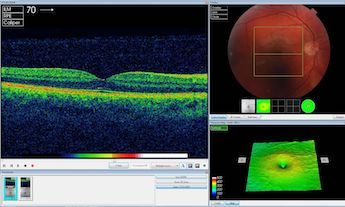

AI tools from DeepMind were able to interpret OCT retinal scans rapidly and accurately.

DeepMind's solution combines two different neural networks. The first, known as the segmentation network, analyses the OCT scan to provide a map of the different types of eye tissue and the features of disease it sees, such as hemorrhages, lesions, irregular fluid or other symptoms of eye disease - a process the company describes as "allowing eyecare professionals to gain insight into the system’s thinking."

The second network, known as the classification network, analyses this map to present clinicians with diagnoses and a referral recommendation. Crucially, the network expresses this recommendation as a percentage, allowing clinicians to assess the system’s confidence in its own analysis.